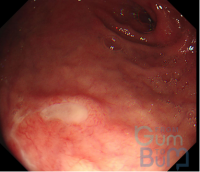

Which classification can be used in Esophageal Candidiasis?

candidia